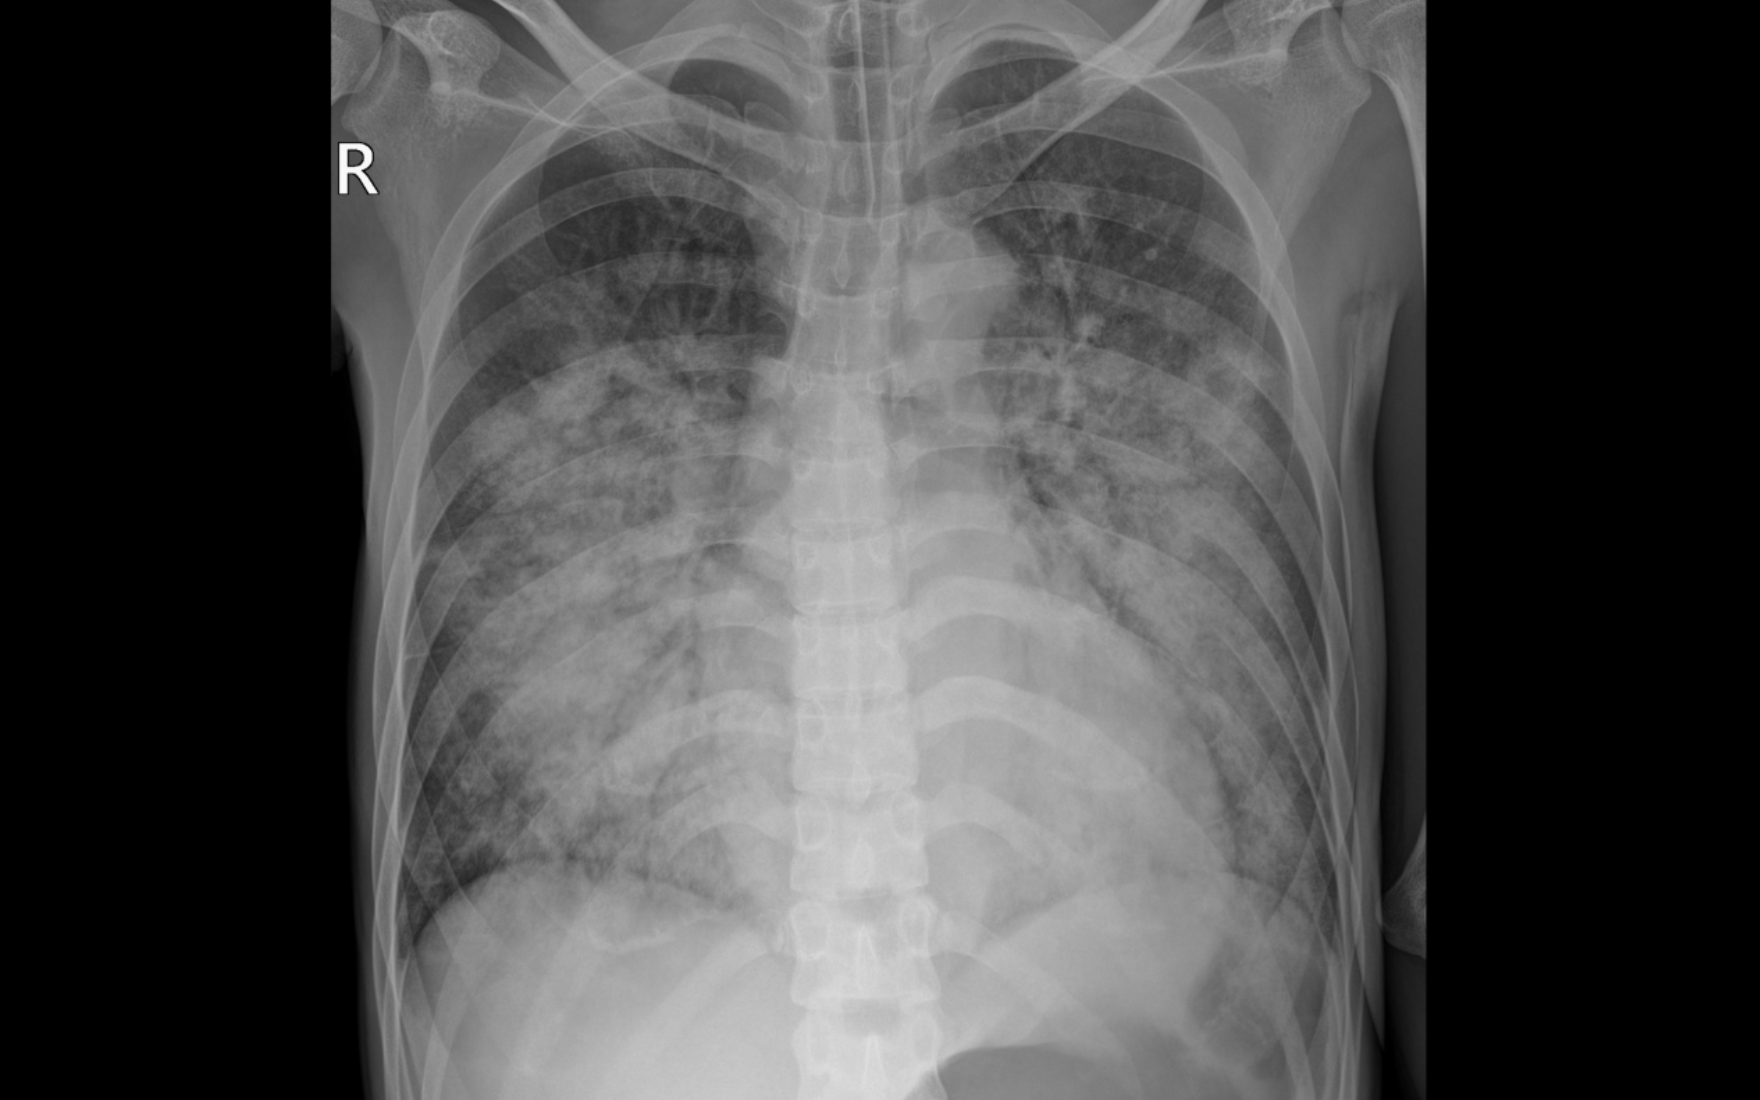

Phim chụp X quang thể hiện tổn thương mờ, lan tỏa 2 phổi của bệnh nhân

Các kết quả cho thấy người bệnh đang rơi vào suy tim cấp nặng, chức năng co bóp tim suy giảm nghiêm trọng, chỉ còn 31%, kèm theo nhiễm trùng máu và viêm phổi nặng, khiến suy hô hấp tiến triển nhanh với nguy cơ tử vong cao. Trước diễn biến phức tạp, người bệnh được chuyển theo dõi sát sao tại Khoa Hồi sức Tích cực, đặt ống nội khí quản sớm đồng thời phối hợp chặt chẽ với các phác độ điều trị suy tim, kiểm soát nhiễm trùng và hỗ trợ hô hấp.